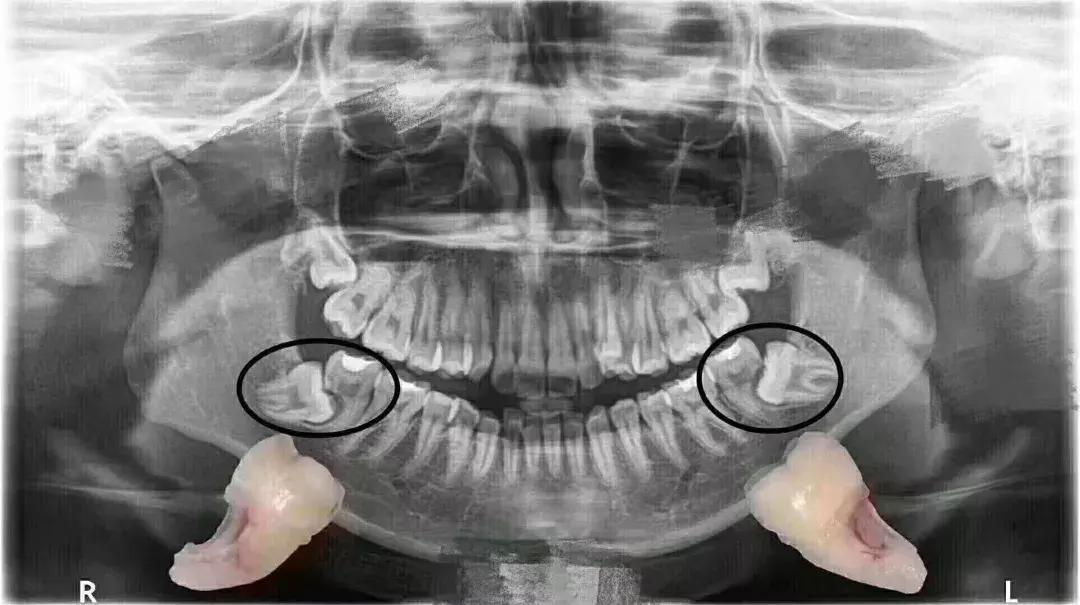

智齒圖片解析

為了更好地了解智齒的形態(tài),我們搜集了一些智齒的圖片供大家參考,這些圖片展示了不同角度下的智齒形態(tài),包括智齒的側(cè)面、正面和咬合面等,通過(guò)仔細(xì)觀察這些圖片,大家可以更加直觀地了解智齒的形狀、大小和顏色等特征。

(請(qǐng)?jiān)诖颂幉迦胫驱X圖片)